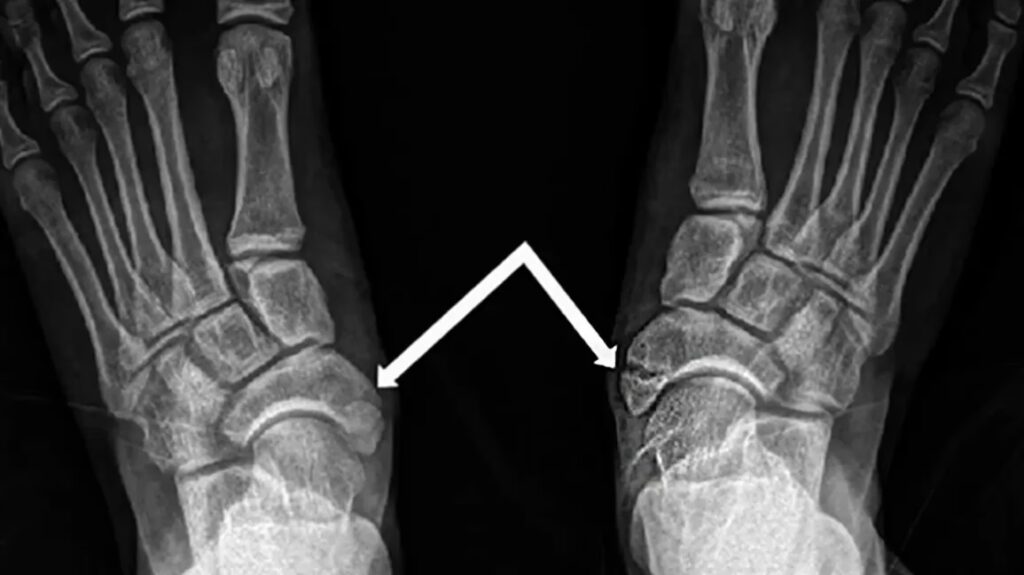

A broken foot, medically termed a fractured foot, occurs when one or more of the 26 bones in your foot suffers a break. These injuries can vary significantly in their nature and severity. They can range from microscopic cracks, often referred to as stress fractures, which develop over time due to repetitive force, to a complete break of a single bone, or even multiple bones. In severe cases, a bone might break into several pieces, or even pierce through the skin, known as an open fracture. The location and severity of the fracture are critical factors in determining the appropriate treatment and recovery prognosis.

A: A fracture is a break in a bone, while a sprain is an injury to ligaments, the tough fibrous tissues that connect bones to other bones. Both can cause pain, swelling, and bruising, making it difficult to differentiate without medical imaging (like an X-ray). Fractures often present with more intense, immediate pain and sometimes deformity, but only a healthcare professional can provide an accurate diagnosis.